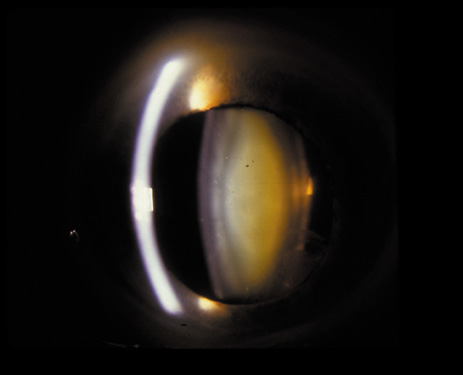

Nuclear cataracts tend to progress slowly. The refractive index of the lens changes as the nucleus progressively hardens, which usually results in increasing myopia.20,21 In some patients this is accompanied by optical distortion, especially of distant images, while near vision remains unaffected. A nuclear cataract is best seen with the narrow-beam direct illumination employed by the slit-lamp, which reveals the color and generalized haze or opalescence of the nucleus. In the early stages, the two halves (cotyledons) of the embryonic nucleus remain visible (Fig. 3). Later the entire nucleus appears as a homogeneous mass in contrast to the cortex (Fig. 4). Retroillumination may show the “oil droplet” effect (Fig. 5). Sometimes one may notice crystals in the lens nucleus (known as a Christmas tree cataract; Fig. 6A and B).

Fig. 4. Advanced nuclear cataract. Note the homogeneous nuclear opacity.

Fig. 5. “Oil droplet” appearance of a pure nuclear cataract seen on retroillumination examination.